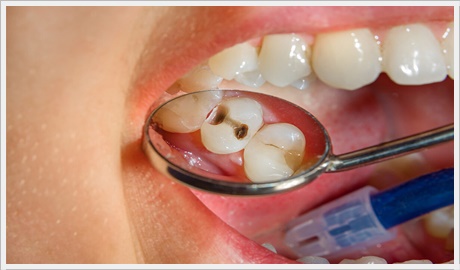

Dis Curugu Nedir Tedavisi Nasil Yapilir Dentvizyon

Konservatif Dis Tedavisi Dis Estetigi Gulus Estetigi

Konservatif Dis Tedavisi Dis Estetigi Gulus Estetigi